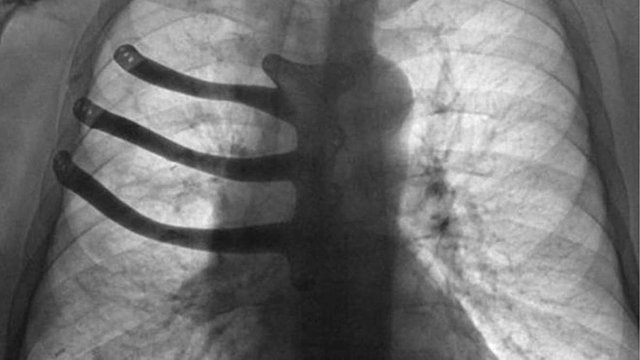

Як зазначається, 71-річному Пітеру Меггзу видалили три ребра і половину грудної кістки, помістивши замість них протез. За словами медиків, ракова пухлина розрослася завбільшки з тенісний м'яч і її видалення спричинило великі пошкодження грудної клітки. Операція тривала вісім годин. Її провели в госпіталі Моррісон у Суонсі - другому за величиною місті Уельсу.

Зазвичай в таких випадках хірурги відливають протез із спеціального медичного цементу. Але завдяки технології 3D-друку лікарі змогли виготовити для хворого індивідуальний імплантат з титанового сплаву. «Потрібно було вирізати сильно розвинену пухлину, а разом з нею видалити частину грудної кістки і три ребра», - розповів хірург-кардіолог Айра Голдсміт.

Титановий імплантат виготовили заздалегідь - по моделі, яку підготував доктор Голдсміт. Йому асистував хірург-консультант Томас Брегг. Операція пройшла успішно, пацієнт каже, що почувається добре.